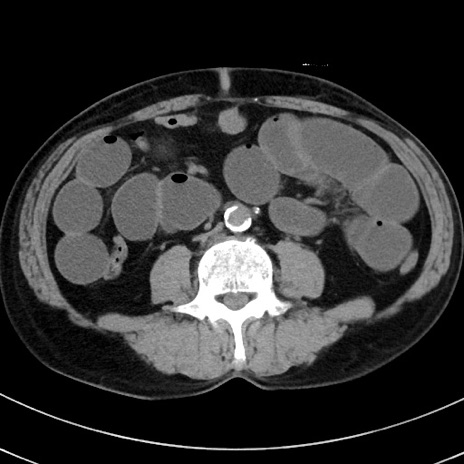

症例38(横断像)

【症例】70歳代 男性

【主訴】腹痛・嘔吐

【現病歴】昨晩より、嘔吐・腹痛あり。今朝になっても嘔吐あり。来院。

【既往歴】心臓バイパス手術、開腹胆摘、腸閉塞

【身体所見】BP 107/71mmHg、HR 116/min、腹部:平坦、軟、下腹部に軽度圧痛あり。反跳痛なし。

【データ】WBC 15100、CRP 0.32